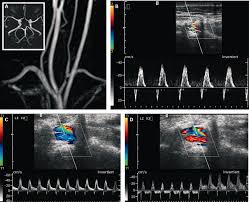

The left vertebral artery spectral wave doppler is seen below the baseline as compared to both left CCA and right vertebral artery. Subclavian steal syndrome occurs secondary to a proximal stenosing lesion or occlusion in the subclavian artery. Features are characteristic of complete left subclavian steal syndrome Features are characteristic of complete left subclavian steal syndrome.

Features are characteristic of complete left subclavian steal syndrome Features are characteristic of complete left subclavian steal syndrome.

Subclavian steal syndrome SSS is a condition secondary to an occlusion in the proximal subclavian artery which leads to upper-extremity blood supply to be derived by reversal of flow within the ipsilateral VA. Primary Stenting of Right-Sided Subclavian Artery Stenosis Presenting as Subclavian Steal Syndrome. Blood is drawn from the collateral circulation which results in reversed blood flow in the ipsilateral vertebral artery. The term subclavian steal describes retrograde blood flow in the vertebral artery associated with proximal ipsilateral subclavian artery stenosis or occlusion usually in the setting of subclavian artery occlusion or stenosis proximal to the origin of the vertebral artery. The subclavian steal syndrome is a condition where hypoperfusion of the cerebrovascular system is caused by occlusion or severe obstruction of the proximal subclavian or brachocephalic artery. Alternatively innominate artery disease has also been associated with. Although a low-grade stenosis is usually asymptomatic and may remain unobserved a. The term subclavian steal was coined by Fisher as the reversed retrograde ipsilateral vertebral blood flow was due to the stealing of blood from the posterior cerebral circulation by the subclavian artery. Since recognition of this syndrome can lead to successful treatment a review by.